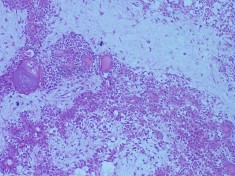

Bệnh nhân nam, 41 tuổi, MP: lồi mắt

Chẩn đoán MP: U hỗn hợp tuyến lệ lành tính

Bệnh nhân lồi mắt xuất hiện 3 năm, tăng nhanh trong vòng 1 năm trước vào viện, đẩy nhãn cầu xuống dưới (A). Hình ảnh cắt lớp vi tính có khối tăng ti trọng, bờ dày đều, kích thước 27 x 38 mm (C, D). Bệnh nhân được phẫu thuật cắt bỏ u cả khối gồm cả vỏ (E). Kết quả giải phẫu bệnh là hình ảnh biểu mô và trung mô của u hỗn hợp tuyến lệ lành tính (F: H&E x 100).